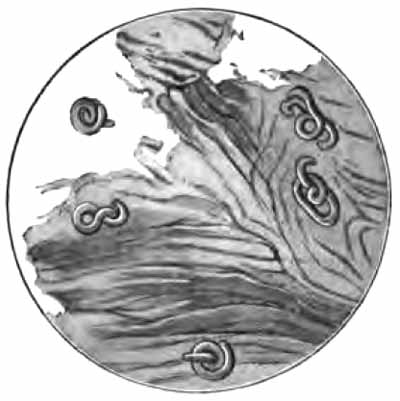

Charcot-Leyden crystals

FIG. 6.—Charcot-Leyden crystals (after Riegel).

[p. 30] 3. Charcot-Leyden Crystals.—Of the crystals which may be found in the sputum, the most interesting are the Charcot-Leyden crystals. They are rarely found except in cases of bronchial asthma, and were at one time thought to be the cause of the disease. They frequently adhere to Curschmann spirals. Their exact nature is unknown.

They are colorless, pointed, often needle-like, octahedral crystals (Fig. 6). Their size varies greatly, the average length being about three or four times the diameter of a red blood-corpuscle.

Other crystals—hematoidin, cholesterin, and, most frequently, fat needles—are common in sputum which has remained in the body for a considerable time.